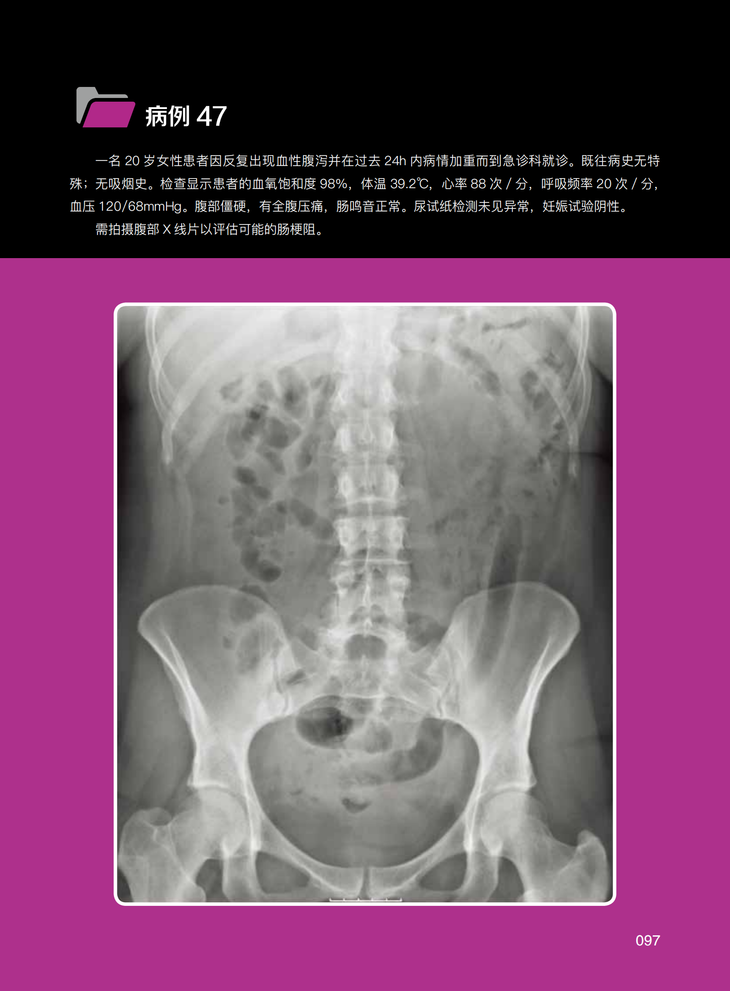

病例47 结肠炎